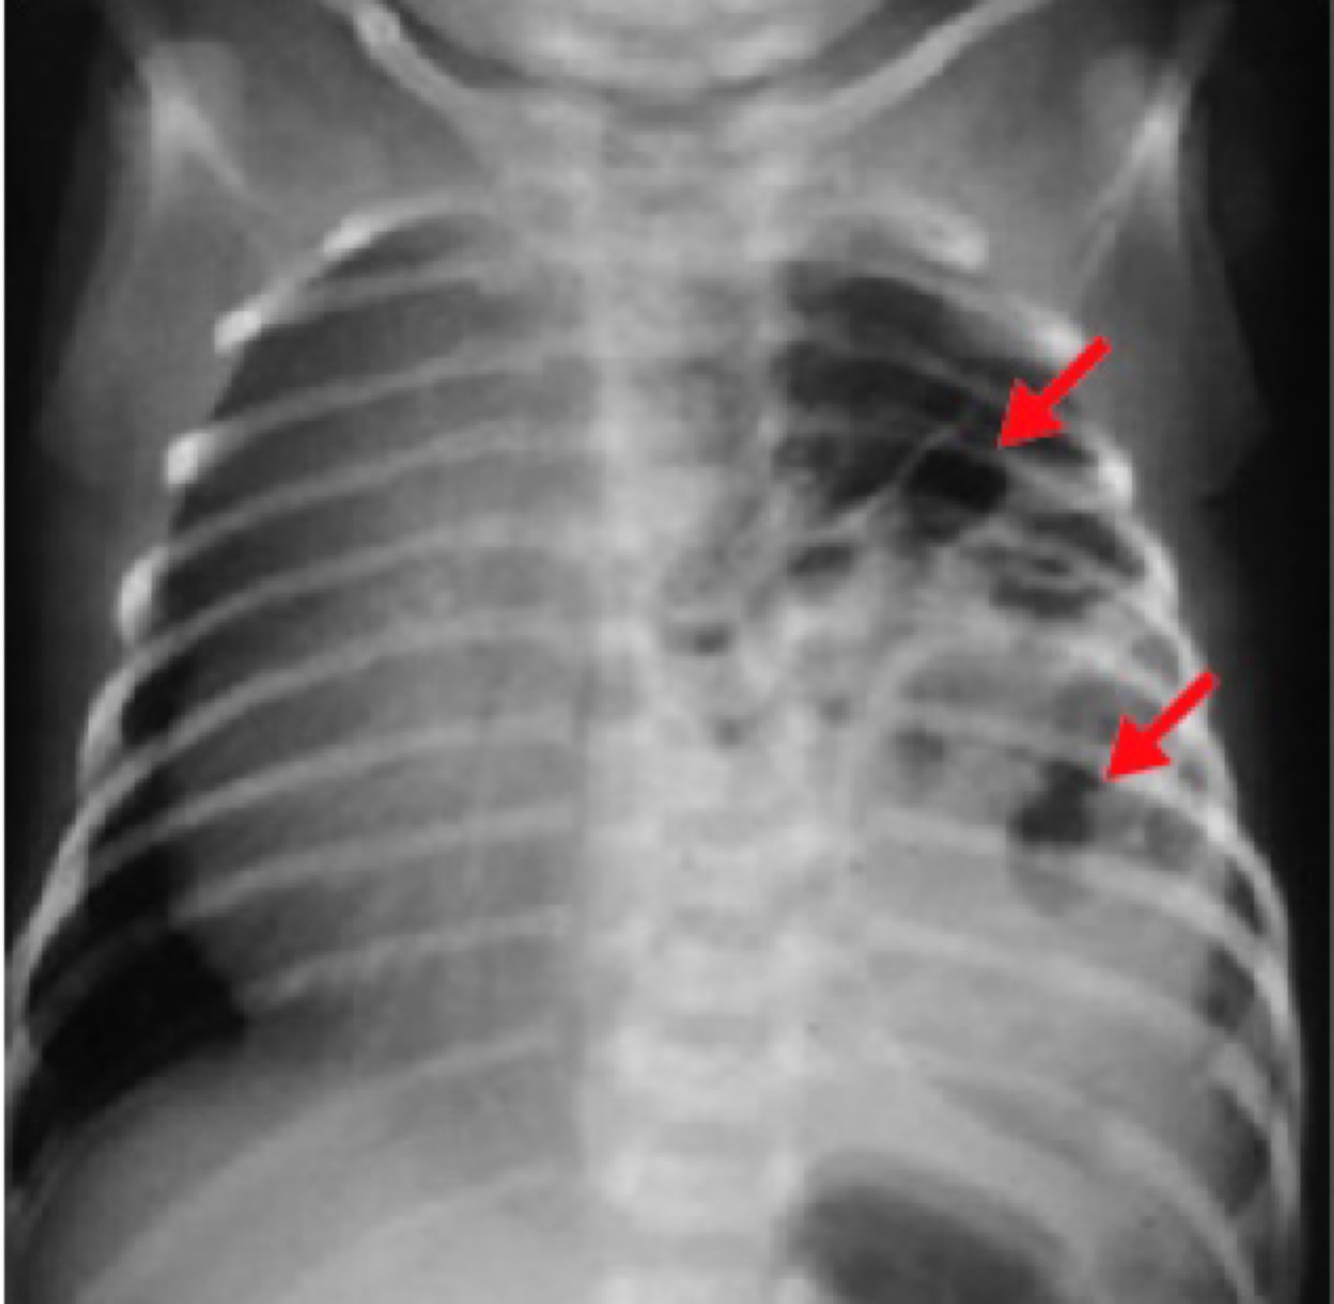

Pulmonary hypoplasia can result from congenital diaphragmatic hernia

congenital diaphragmatic hernia